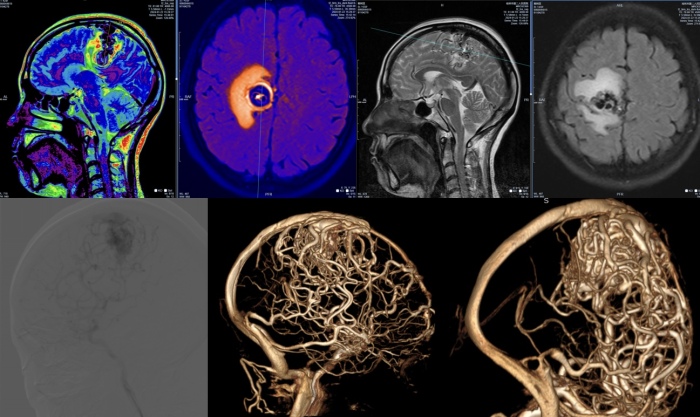

借助MR多模态影像分析处理、DSA AneuFlow血流动力计算,湘雅二医院桂林医院神经外科创新性展开复杂脑血管病多模态一站式术前模拟分析评估,推动了复杂脑血管病术前精准评估与诊疗措施最优解探究,为患者提供更高效、精准的治疗方案。

多模态影像融合及血流动力学构筑分析功能区高级别脑血管畸形